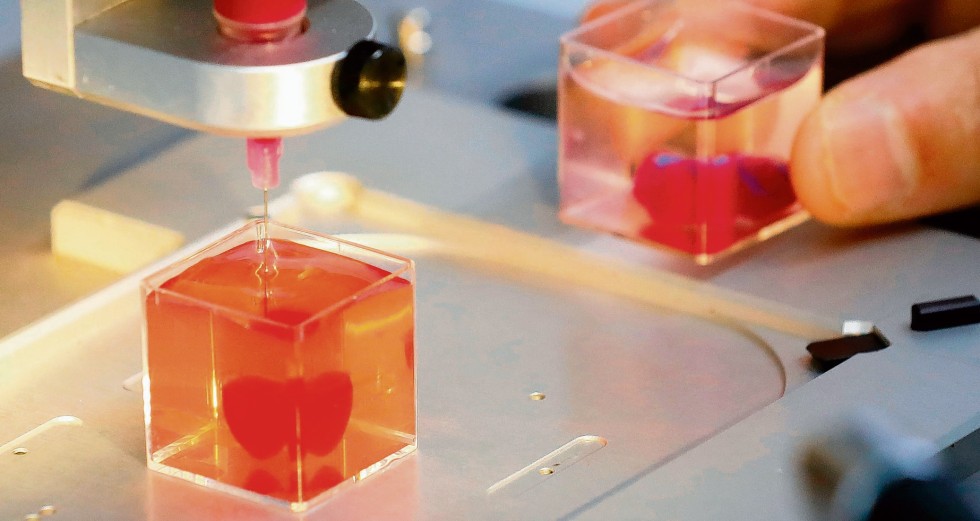

Auch das Miniherz aus Israel wurde bereits mit einer eigenen Blutversorgung ausgestattet. Dafür hatte das Team um Tal Dvir an der Universität Tel Aviv Stammzellen aus dem Fettgewebe eines Probanden isoliert und umprogrammiert. Daraufhin erzeugten die Stammzellen einerseits Herzmuskel- und andererseits Endothelzellen, die die Innenwände von Blutgefäßen bilden.

„Es ist das erste Mal, dass ein vollständiges Herz mitsamt Zellgewebe, Blutgefäßen und Ventrikeln gedruckt wurde“, sagt Dvir. Zwar sei das Organ nur etwa so groß wie eine Kirsche und könne auch nicht schlagen, doch habe sein Team gezeigt, dass mit dieser Technologie im Prinzip auch größere menschliche Herzen hergestellt werden könnten.